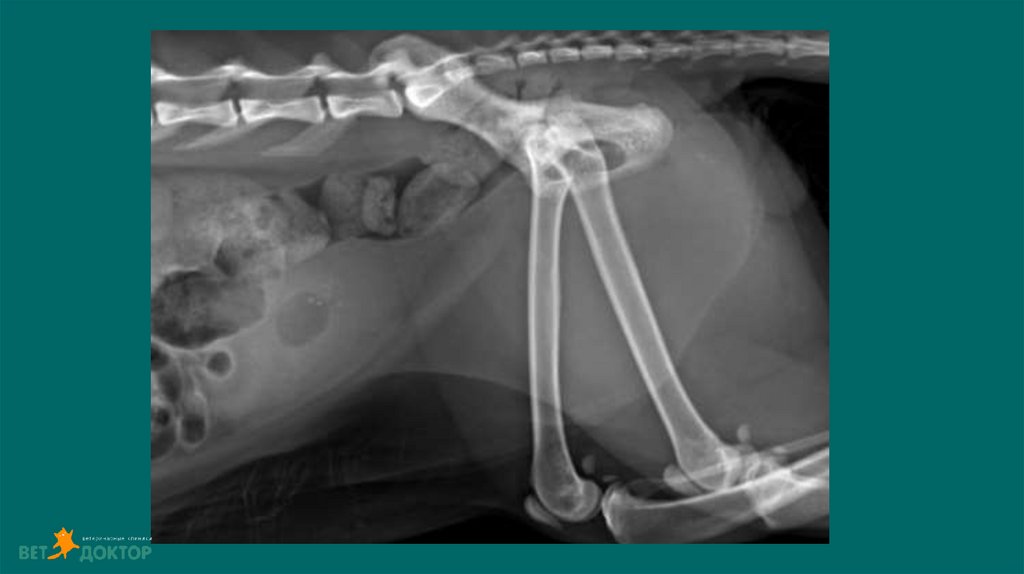

6. Рентгенологические исследования

Размер и симметричность почек, размер и топографию мочевого пузыря, размер и

положение репродуктивных органов.

У собак почки имеют бобовидную форму. Размер в 2,5-3,5 раза превышают длину L 2

У кошек овальная до круглой. Размер почек измеряют на ВД проекции в 2,4-3,0 раза

превышают длину L2

Размер проксимального отдела мочеточника :

Собаки 2-3мм. Кошки 1-2мм

Метод выявления рентгеноконтрастных уролитов (фосфат кальция, оксалат кальция,

струвиты)

Ураты /цистеиновые уролиты рентгенопрозрачны.